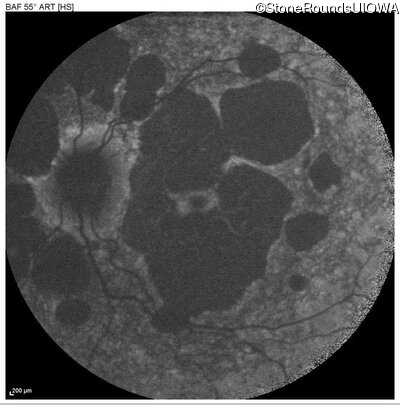

AR Stargardt Disease (IIA)

Age at visit: 51 years

This 51 year old woman first experienced some abnormality in her distance vision when she was 27 years old. She feels that her vision has been stable since that time.

Diagnosis & molecular findings

Disease Gene Allele 1 variant(s) Allele 2 variant(s) Inheritance mode

AR Stargardt Disease ABCA4 Gly1507Arg GGG>AGG IVS42+1 G>A AR